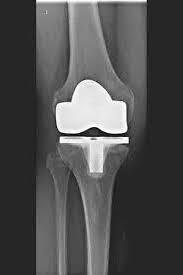

PTG (ARTICULATION ARTIFICIELLE DU GENOU)

L’articulation artificielle du genou remplace la surface cartilagineuse détruite par l’arthrose. L'os sous-jacent du fémur et de la tête tibiale reste intact. Certains comparent une articulation artificielle moderne du genou à un couronnement de dent ; le terme exact est ce qu'on appelle le resurfaçage bicondylien. Entre les nouvelles surfaces sur la partie supérieure et inférieure de la jambe se trouve ce que l'on appelle une incrustation en plastique blanc spécialement durci, qui peut être vue sur l'image radiographique comme la distance entre les pièces métalliques.